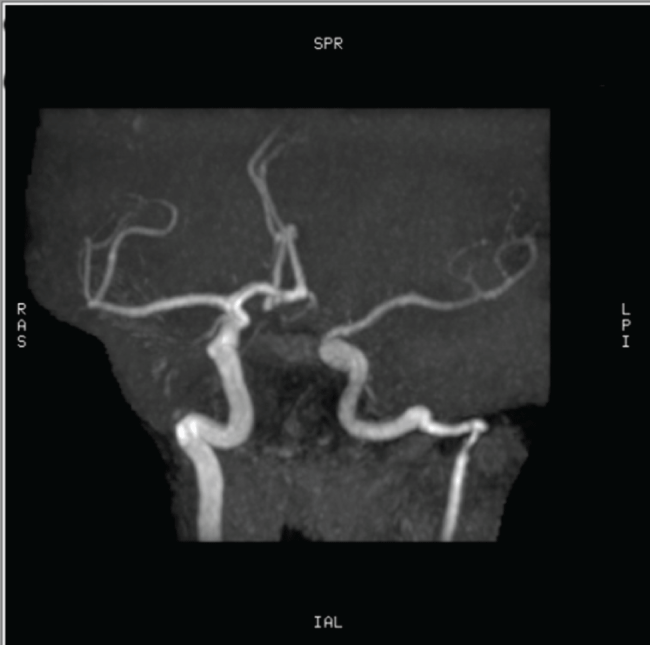

A 50-year-old woman presented with a four-year history of left-sided pulsatile tinnitus and hearing impairment. Otoscopy revealed a reddish mass behind the inferior half of the left tympanic membrane. Audiometric evaluation showed mild conductive hearing loss in the left ear. High-resolution CT scanning of the temporal bone was performed. On the CT scan of the temporal bone, a left-sided aberrant ICA entering the middle ear cavity through an enlarged inferior tympanic canaliculus was observed (Figure 1). The right temporal bone was normal. MRA showed a reduced diameter and lateralization of the left ICA (Figure 2A and Figure 2B). The vertical segment of the ICA was lateral and posterior to a line drawn vertically through the vestibule. Hypoplasia of the A1 segment of left ACA was also identified.

Figure 2a: Magnetic resonance angiography showing reduced diameter and lateralization of the left internal carotid artery (ICA). The right ICA is normal. Hypoplasia of the A1 segment of the left anterior cerebral artery (ACA) is also noted.

Figure 2b: Magnetic resonance angiography showing reduced diameter and lateralization of the left internal carotid artery (ICA). The right ICA is normal. Hypoplasia of the A1 segment of the left anterior cerebral artery (ACA) is also noted.

The misdiagnosis of aberrant ICA can result in fatal bleeding or other life-threatening complications. Suspicion of a retro-tympanic mass in the middle ear necessitates radiographic investigation. CT scan of the temporal bone is considered as one of the most reliable methods to diagnose an aberrant ICA. On CT scan, aberrant ICA is recognized by; an enhanced mass in the hypotympanum, a deficient bony plate along the tympanic portion of the ICA, absence of the vertical segment of the carotid canal, and a reduced diameter of ICA that runs adjacent to the jugular bulb [2-5]. MRA can be used as an additional tool for the definitive diagnosis and it also provides excellent visualization of the intracranial and extracranial circulation. The important features at angiography are; a reduced diameter of the tympanic ICA, the vertical segment of the ICA is lateral to a line drawn vertically through the vestibule [2,5]. In our case, CT and MRA showed all the characteristic features of aberrant ICA. In addition, hypoplasia of the A1 segment of the anterior cerebral artery was identified on MRA. In a review of the literature, we noted various other reports of an aberrant ICA in which hypoplasia of the A1 segment of the ACA was noted as an incidental finding [8-11]. Hypoplasia of the A1 segment of the ACA is reported to be present in 10% of autopsies [12]. The relationship between ipsilateral absence or hypoplasia of the A1 segment and a reduced caliber of the ICA has been further reported by Kane et al. [13] in a study of intracranial MR angiograms.